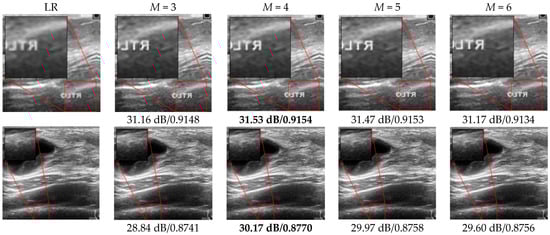

3.2. SR Performance by Varying the FEN Structure

| Dataset | M | Mean PSNR [dB] | Mean SSIM | SR Testing Time |

|---|---|---|---|---|

| Dataset A [32] | 3 | 33.28 | 0.9171 | 0.275 s |

| 4 | 33.54 | 0.9190 | 0.290 s | |

| 5 | 33.50 | 0.9128 | 0.293 s | |

| 6 | 33.44 | 0.9178 | 0.310 s | |

| Dataset B [33] | 3 | 31.72 | 0.8653 | 0.266 s |

| 4 | 31.90 | 0.8677 | 0.284 s | |

| 5 | 31.67 | 0.8669 | 0.291 s | |

| 6 | 31.62 | 0.8668 | 0.296 s |